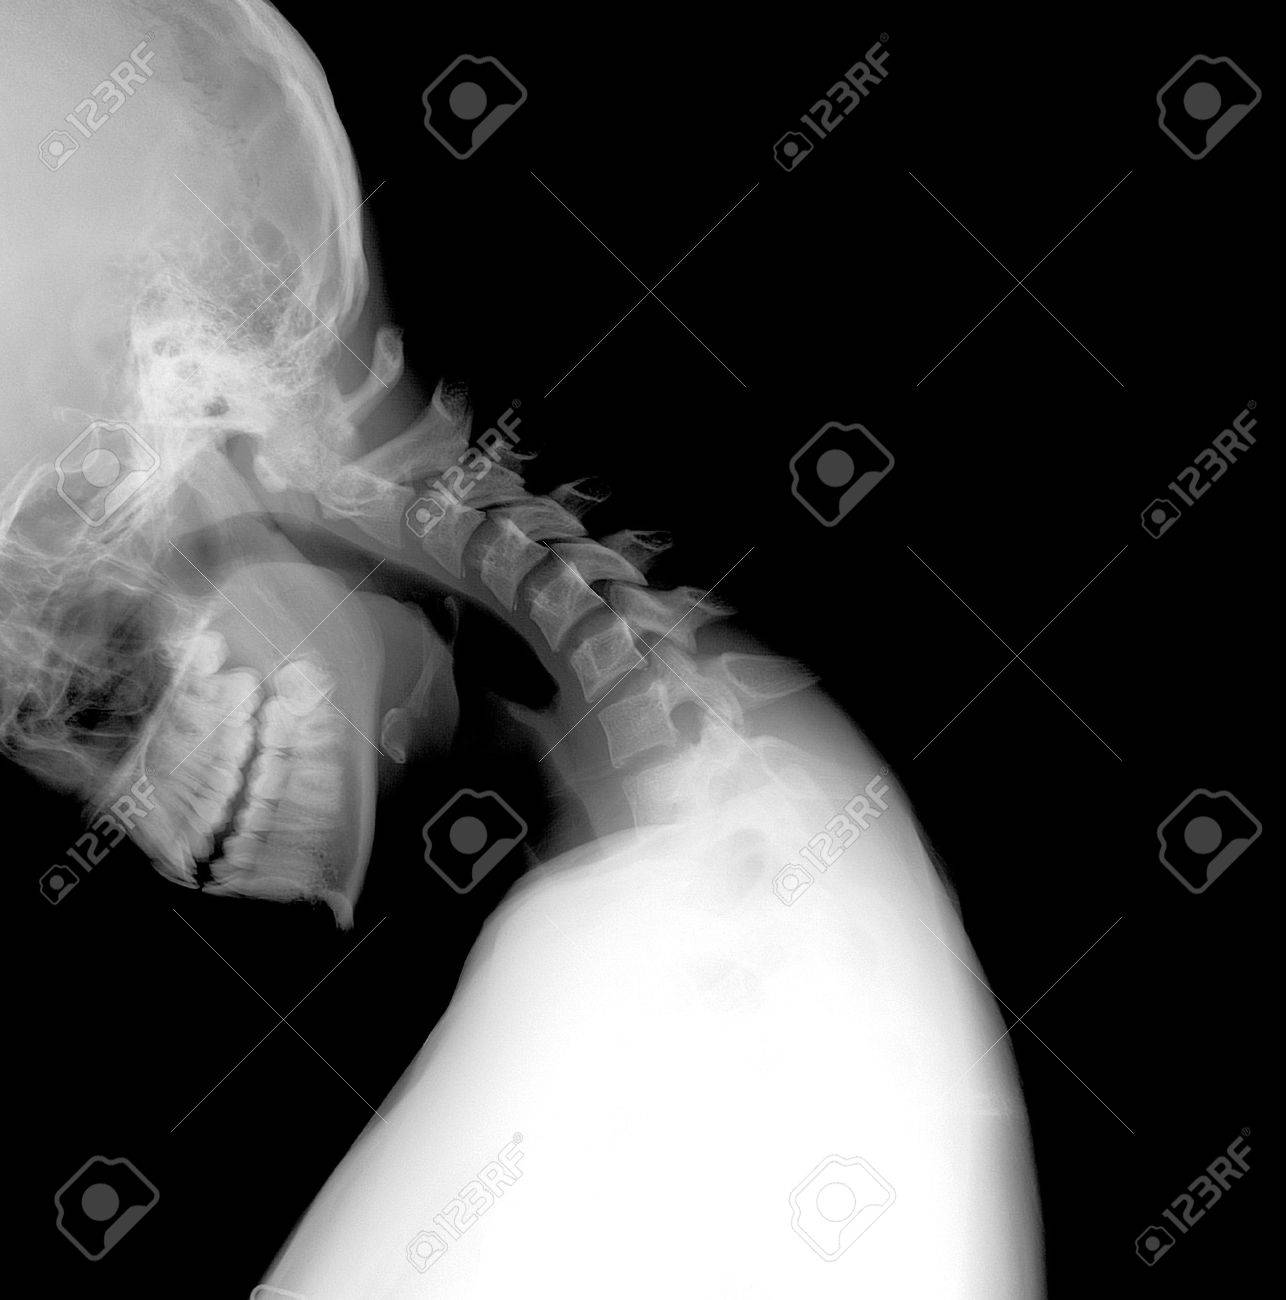

Immagini Stock Radiografia Del Collo E Del Rachide Cervicale Test Funzionale Laterale Lat Instabilita Image

Radiografia Della Colonna Cervicale Con Proiezioni Dinamiche Iltuoesame It

Testa Radiografia Collo Testa Collo No La Trauma Raggi X Mostra Canstock